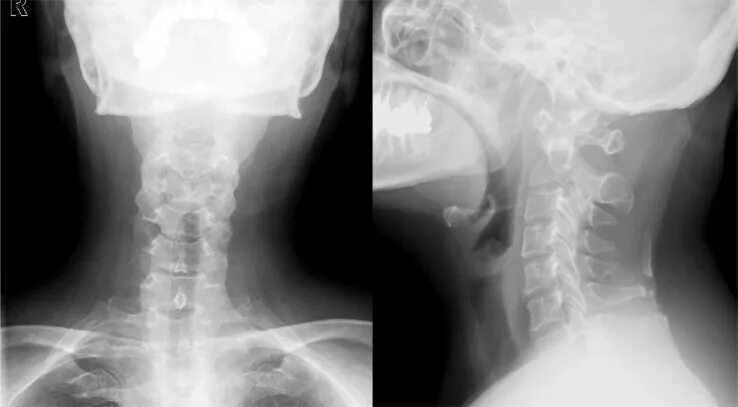

Шейный подвывих у взрослых